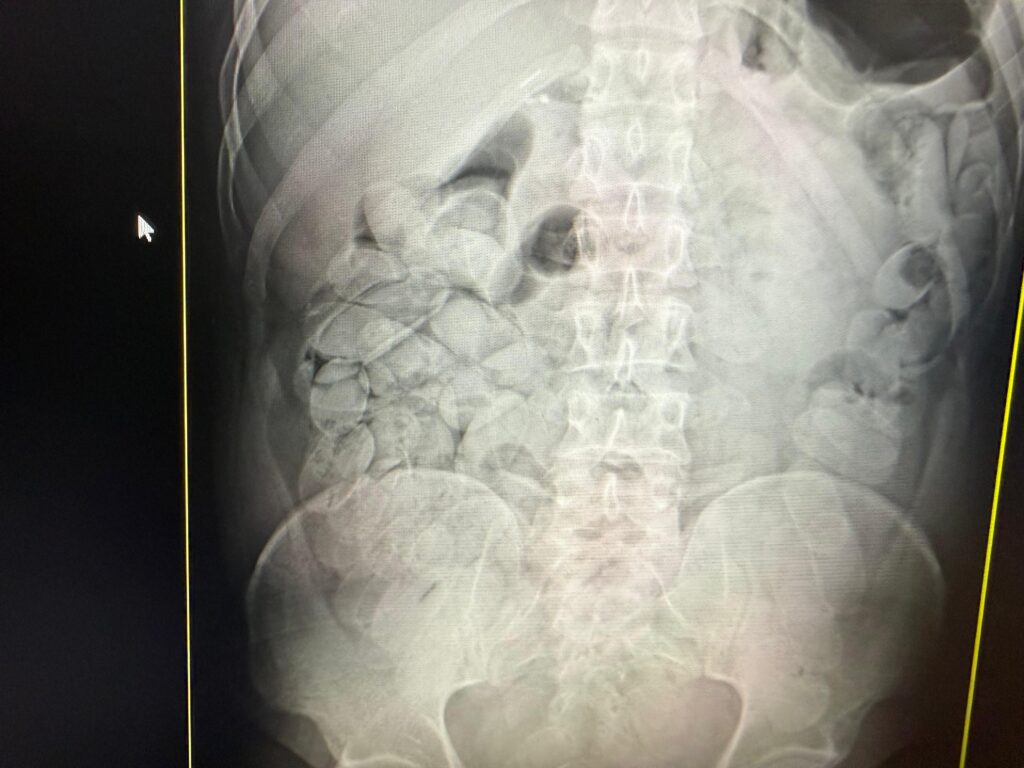

Com apoio de cães farejadores da Receita Federal e da Marinha, foi identificada a presença de cápsulas de cocaína escondidas em frascos de xampu. Além disso, exames médicos confirmaram que 17 passageiros bolivianos haviam ingerido cápsulas da droga. Ao todo, 18 pessoas foram detidas, resultando na apreensão de cerca de 20 quilos de substância análoga à pasta base de cocaína, com prejuízo estimado em R$ 1 milhão ao crime organizado.

Enquanto um dos detidos já foi encaminhado à Polícia Federal, os demais permanecem sob custódia no pronto socorro municipal até expelirem todo o entorpecente, quando também serão entregues à polícia judiciária. Paralelamente, o Ministério da Agricultura reteve aproximadamente duas toneladas de mercadorias de origem animal e vegetal sem documentação legal.